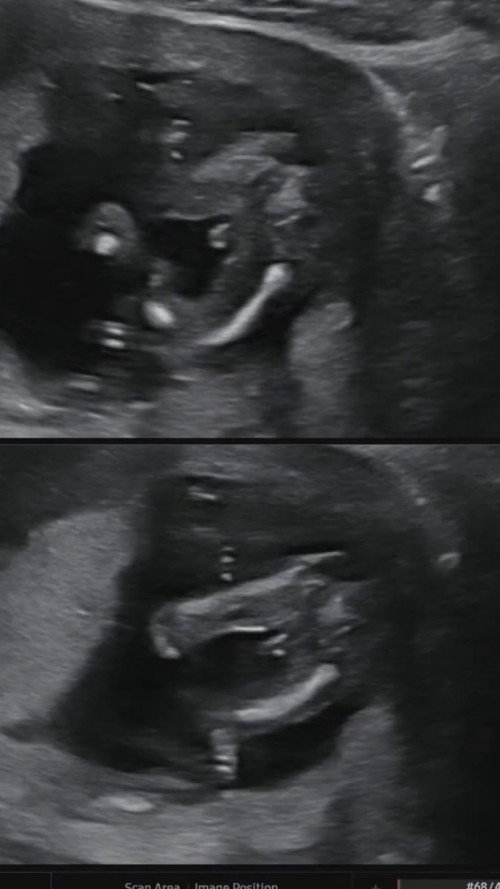

แม่ๆรู้สึกว่าลูกดิ้นลูกตอดตอนกี่ W คะ ทางนี้#ท้องแรก #ขอบคุณมากๆค่ะสำหรับคำตอบ 17wมีความรุ้สึกเหมือนมีปลาว่ายน้ำเล่นยุในท้อง แปปก็หาย นานๆมาทีแต่่ไม่รุ้ว่าใช่มั้ย #ท้องแรก17w